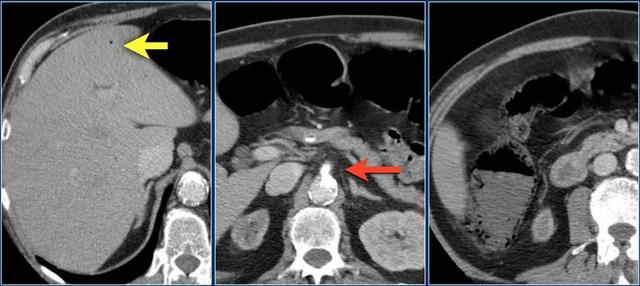

下图是由于SMV血栓形成而导致肠缺血的病人(红色箭头)。

注意肠系膜静脉充血(黄色箭头)。